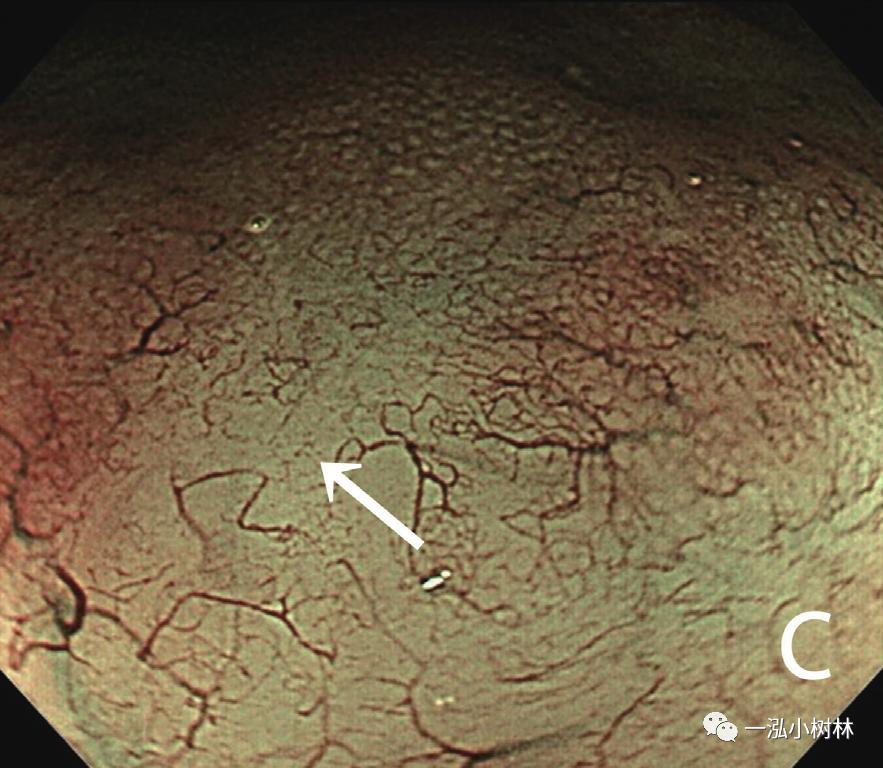

内镜检查(图1):胃黏膜整体粗糙、弥漫性隆起,易出血。在胃体下部、胃窦部黏膜的粗糙明显,散在小隆起,一部分也发现了较大的隆起性变化。ME-NBI视察即使残留着接近正常的腺管,表面微细结构的消失也很明显,在褪色区域也发现了血管的扩张和蛇行、腺管结构的紊乱。

图1c ME-NBI 胃体下部褪色区域中不能识别白区,微小血管的密度降低很明显(箭头)。(问题:NBI放大表现如何与MALT淋巴瘤鉴别)